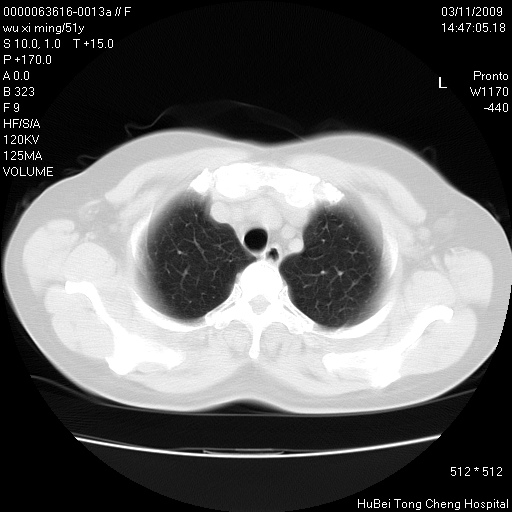

患者 女,51岁。因“胆囊炎,胆囊结石”,行常规术前胸部x线检查发现:右上肺结节病灶,建议行进一步检查。患者无咳嗽、咳痰及咯血等呼吸道症状,近期出现背部疼痛不适。

胸部ct轴位平扫(层厚10mm,螺距1.5,重建间隔10mm;部分层面:层厚3mm,螺距1.0,重建间隔3mm),图像如下:

考虑右肺癌肺内转移!

1、周围型肺癌。(毛刺正、血管束集征,分叶。)

集束征,胸膜牽拉征,毛刺,淺分葉高度提示ca.